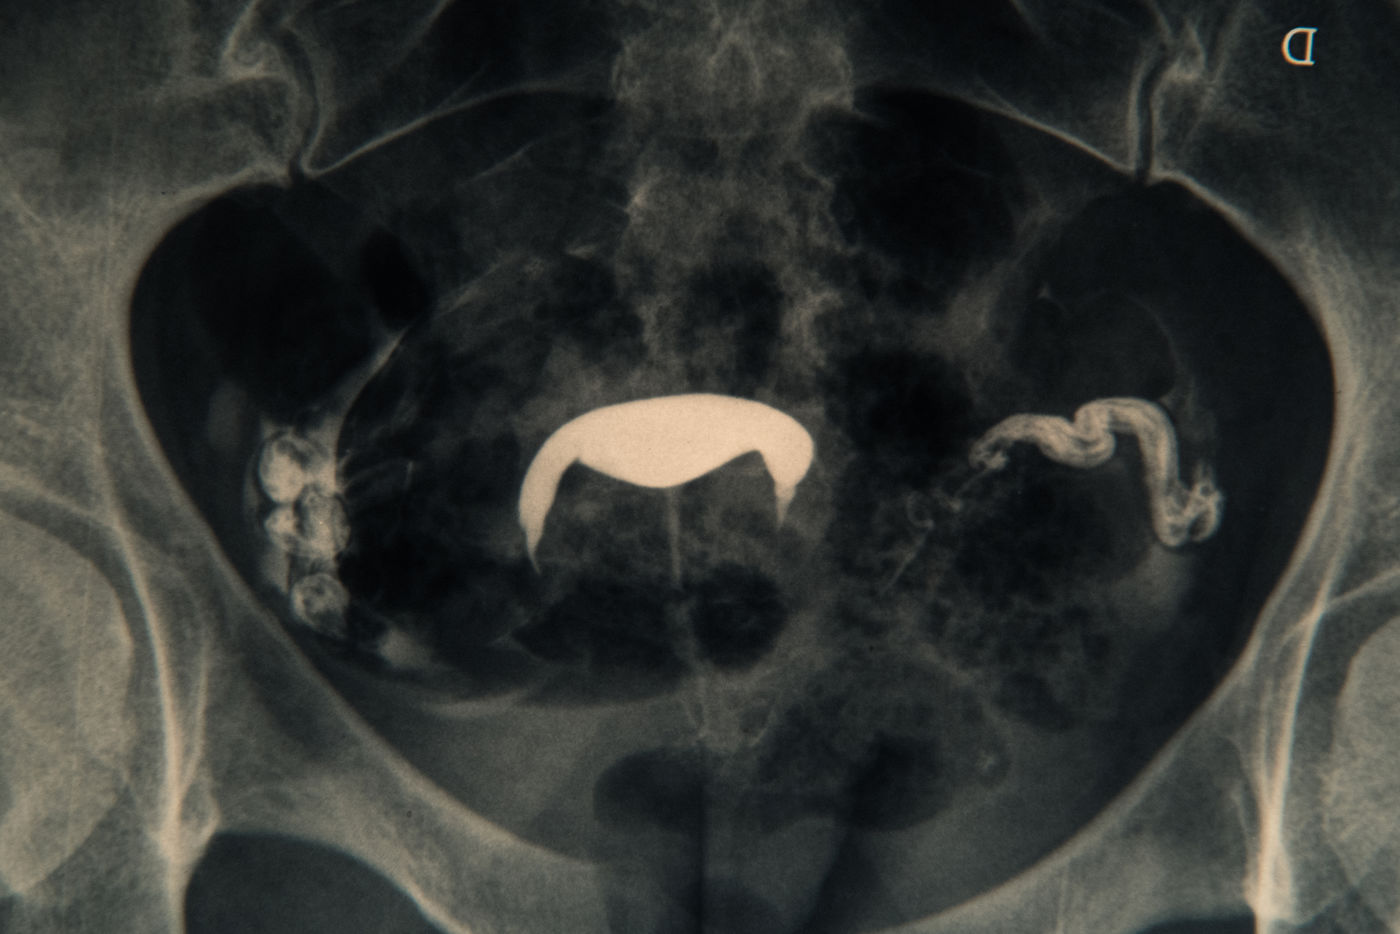

Il est question d'intimité, de non maternité et de mes ovocytes fraîchement congelés.

mon endométriose et d'une rupture il y a plusieurs années 1 mois avant une fiv.

Hopes in the freezer - Fertility preservation

It's about intimacy, non-pregnancy and my freshly frozen oocytes. My

endometriosis and a rupture several years ago 1 month before a ivf. T